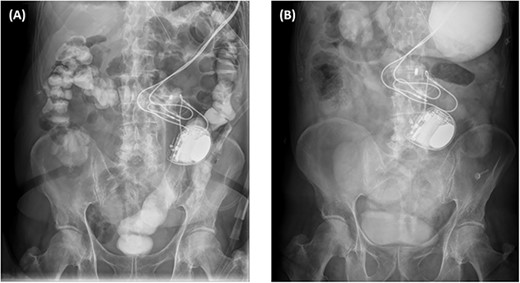

For the first and second hospital admissions, he was managed non-operatively with nil-per-oral, nasogastric tube decompression, intravenous fluids and electrolytes. He successfully passed Gastrografin follow-through into the colon (Fig. 3A). His diet was then progressed and he was discharged home. For the third admission, he did not pass Gastrografin follow-through (Fig. 3B). His treatment was escalated for several indications, including the frequency of SBO recurrences, suspected intraperitoneal migration of the ICD, non-progression of Gastrografin follow-through and non-resolution of obstructive symptoms. He underwent a laparotomy to surgically relieve the mechanical obstruction. Intraoperatively, dense matted adhesions were found between loops of small bowel in the right iliac fossa. Although the ICD was freely floating within the peritoneal cavity, but it did not cross to the right side to have direct involvement with the mechanical transition point. Extensive adhesiolysis was performed to release the mechanical transition point of the small bowel. The ICD was then resecured in a new retrorectus pocket on the left abdominal wall. His postoperative recovery was uneventful and he was discharged home a week later.

X-ray plain films of the abdomen showing passage of Gastrografin into the colon and rectum during the first admission (A); and the non-progression of Gastrografin in the stomach during the third admission (B).